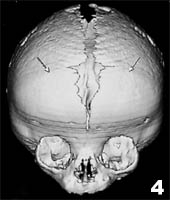

5.短頭畸形 是兩側冠狀縫過早骨化所致。兩側冠狀縫閉合後前額對稱性扁平故又稱為扁頭畸形或寬頭畸形,約占14.3%。病人頭顱兩側冠狀縫骨化造成顱骨前後徑發育障礙和代償性橫徑增寬及顱頂抬高,故表現為頭顱增寬,前額寬平,顱中窩擴大眼眶變淺眶嵴發育不良眼球明顯突出,如同“金魚眼”。

患兒出生後幾周即可出現明顯的畸形額骨上半部高而寬,下半部後縮,扁平,有時凹陷,高而寬的額骨上半部常呈球形突起在面結構之上;下半部後縮將鼻骨牽向後方而使鼻樑下陷。鼻咽腔變小有時顱底及硬齶常有畸形,病兒常有反覆上呼吸道感染骨化的冠狀縫觸及呈念珠狀骨結節。

5.短頭畸形 可見兩側冠狀縫處骨質密度增高,顱底改變為顱前窩縮短而豎起,蝶骨小翼高高抬起往上往後偏斜,翼穴抬高而使顳窩加深。眼眶容積變小。